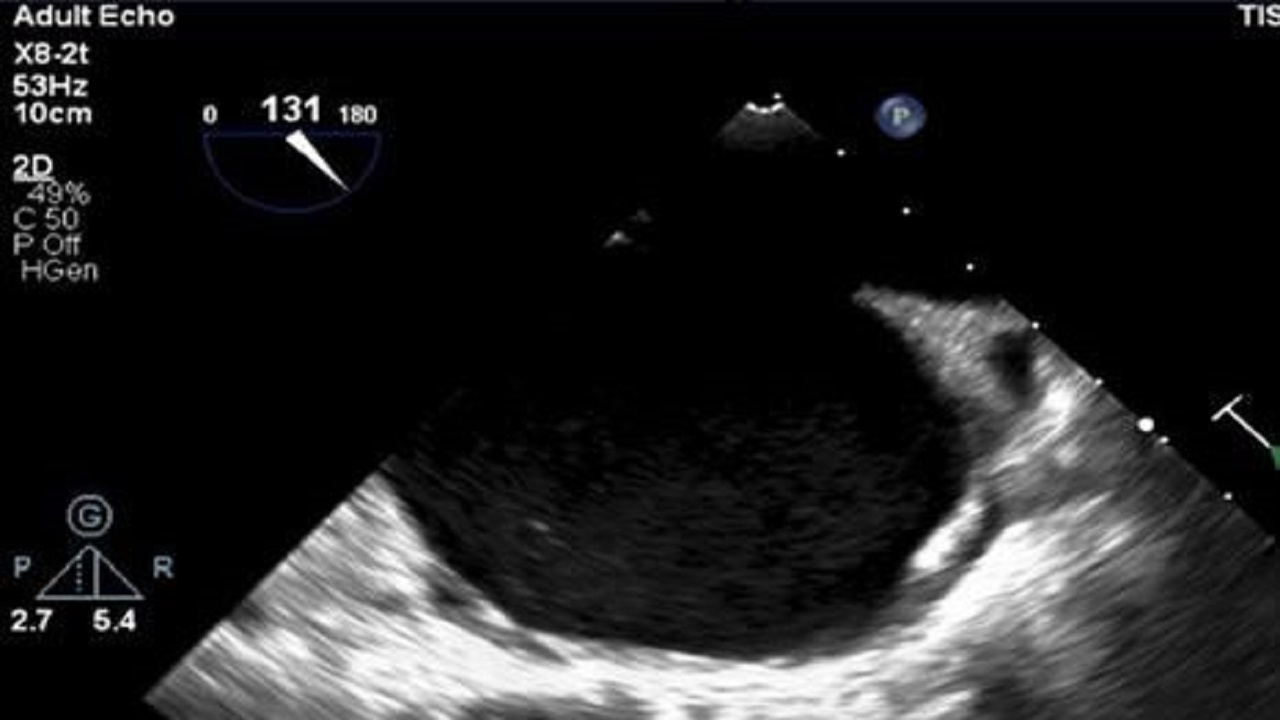

إنقاذ حياة مريضة حامل تعاني من القلب